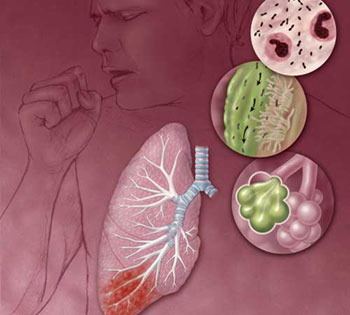

الالتهاب الرئوي – التهاب الرئة Pneumonia

ما هو الالتهاب الرئوي ؟

التهاب الرئة هو عبارة عن التهاب في الحويصلات الرئوية، التي تمتليء بسائل صديدي، وبذلك يجد الاكسجين صعوبة في الانتقال من الحويصلات إلى الأوعية الدموية، وإذا قلت نسبة الاكسجين في الدم فإن الخلايا لا تستطيع أداء عملها على الوجه المطلوب.

أسباب المرض:

إن إلتهاب الرئة لا يرجع لسبب واحد، وإنما هناك أكثر من ثلاثين مسببآ يمكن تصنيفها كالتالي:

– التهاب بكتيري (Bacterial pneumonia)

– إلتهاب فيروسي (Viral pneumonia)

– ألتهاب رئوي لانوعي (Atypical Pneumonia) بالمتفطرات الرئوية (Mycoplasma Pneumonia)

– التهاب رئوي بسبب جراثيم معدية أخرى مثل الفطريات